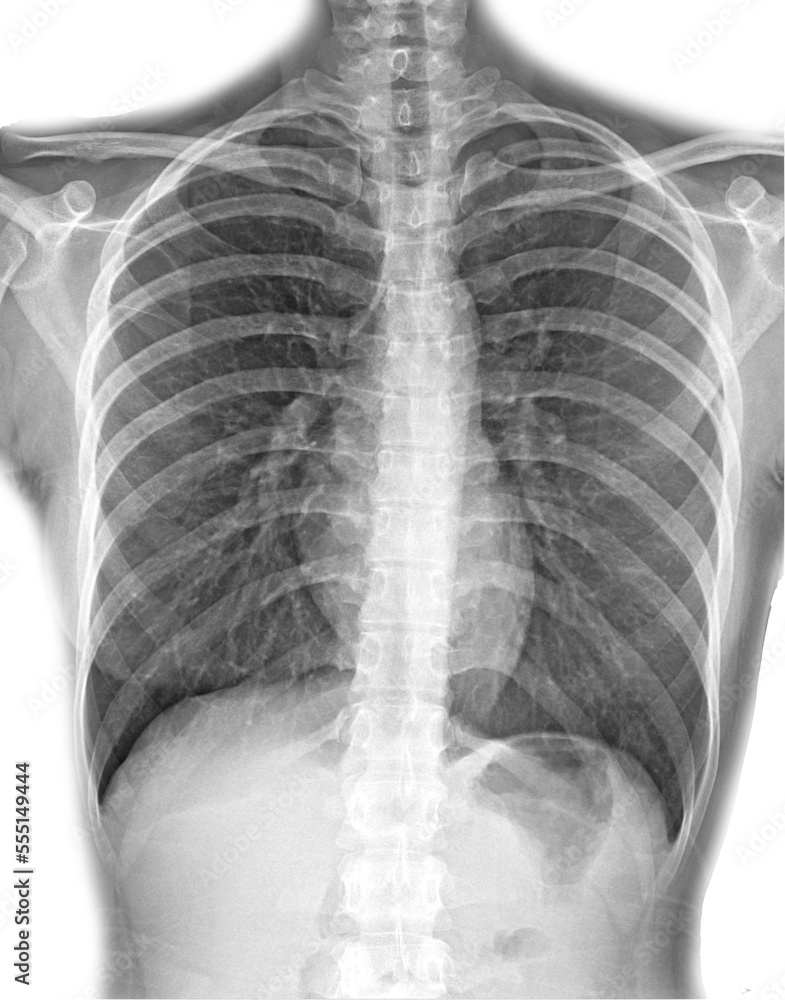

chest xray, pneumonia, emphysema, pulmonology, diagnosis of diseases Chest X Ray Adequate Exposure Always assess inspiration and lung volumes. The space between the medial. Left hemidiaphragm visible to the spine and vertebrae visible behind the heart. Incomplete inspiration can lead to exaggeration of lung markings and heart size. The left hemidiaphragm should be visible to the edge of the spine. Cxr is a quick, noninvasive,. Loss of the hemidiaphragm contour or of. In. Chest X Ray Adequate Exposure.

Pneumonia ( film chest xray show alveolar infiltrate at right middle Chest X Ray Adequate Exposure The interpretation of a chest film. Incomplete inspiration can lead to exaggeration of lung markings and heart size. Cxr is a quick, noninvasive,. Always assess inspiration and lung volumes. The left hemidiaphragm should be visible to the edge of the spine. The space between the medial. In fact every radiologst should be an expert in chest film reading. Left hemidiaphragm. Chest X Ray Adequate Exposure.